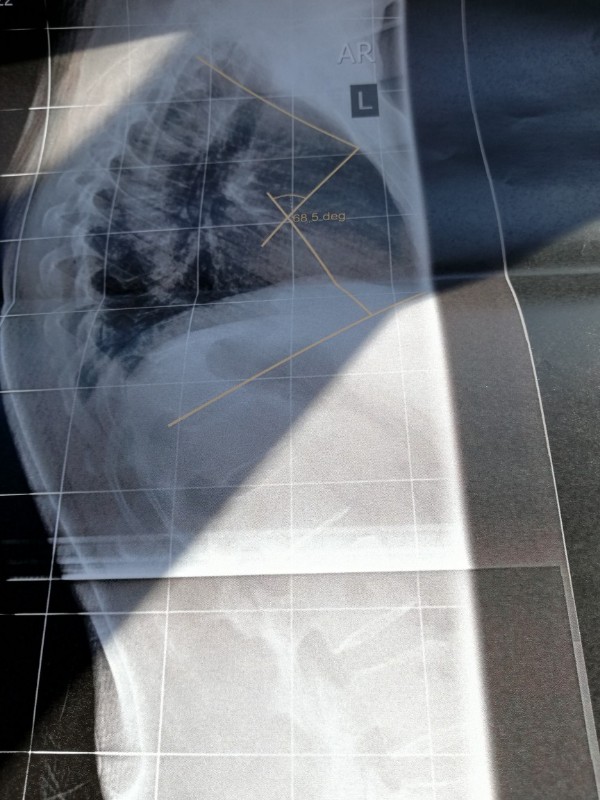

Nachdem ich gestern bei Dr. AL Alwan in Bottrop war, bin ich heute direkt in Oberhausen zum Röntgen der seitlichen Wirbelsäule gefahren. Dr. Al Alwan ist der Ansicht meine Beschwerden könnten von einer Kyphose kommen. Ich bin 54 Jahre alt und habe seit ca 2 Jahren teilweise unerträgliche Schmerzen. Meine Hausärztin ist der Meinung die Schmerzen sind somatoform und mein bisheriger Orthopäde löst mir regelmäßig Blockaden und rät mir zu Sport und Yoga. Leider werden die Schmerzen dadurch schlimmer. Ein MRT 2018 ergab eine leichte Skoliose und eine leichte Kyphose. Leider konnte ich heute mit keinem Arzt über das Röntgenbild sprechen. Es sind Winkel mit 68,5 deg eingezeichnet. Sagt das jemanden was? Es steht nichts von Cobb o. ä. dabei. Ich bin ziemlich ratlos ob das die Ursache der Schmerzen sein könnte. Freue mich über jede Erfahrung oder Tipp von euch. Falls es klappt lade ich mal 2 Bilder hoch. LG und ein schönes, sonniges Wochenende

68,5 Grad könnte sich auf die Hyperkpyhose beziehen, eine normale BWS Kyphose liegt im Bereich 25-40 Grad.

Dr. AL Alwan war nach der Untersuchung der Meinung, dass die Skoliose nicht sonderlich ausgeprägt wäre und mein Rücken sichtbar rund sei. Deshalb die Überweisung zum Röntgen um die Kyphose zu vermessen. Allerdings wurde nur eine seitliche Aufnahme der gesamten Wirbelsäule gemacht. Den Ausdruck und eine CD vom BWS - MRT von 2018 habe ich in seinen Briefkasten geworfen, ich denke nächste Woche weiß ich mehr. Mir ist nur nicht klar ob die 68,5 ged mit Cobb gleichzusetzen sind